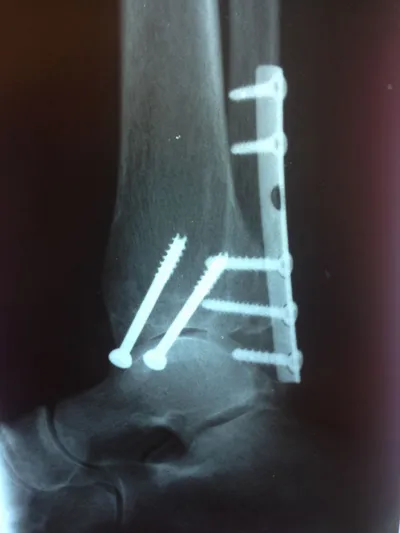

Both the lateral and medial malleolus with fractures with the lateral malleolar fracture classified as a Weber B (at the level of the ankle joint) and the medial malleolar fracture almost transverse (Left x-ray). This is indicative of a Supination External Rotation (SER IV) injury. The fractures are repaired using open reduction with internal fixation (ORIF) technique and fixated with screws and a surgical fractue plate located at the fibular (Right x-ray).

Below is the same patient seen above after surgical repair with open reduction and internal fixation with screws for the medial malleolar fracture and screws and plates for the lateral mallolar fracture. Note the even joint spacing across the ankle mortise after correction (left) that is not evenly spaced in the pre-surgical picture (above right).

Pre and Post Op X-rays of Bimalleolar Fracture Fixated with Plate and Screws